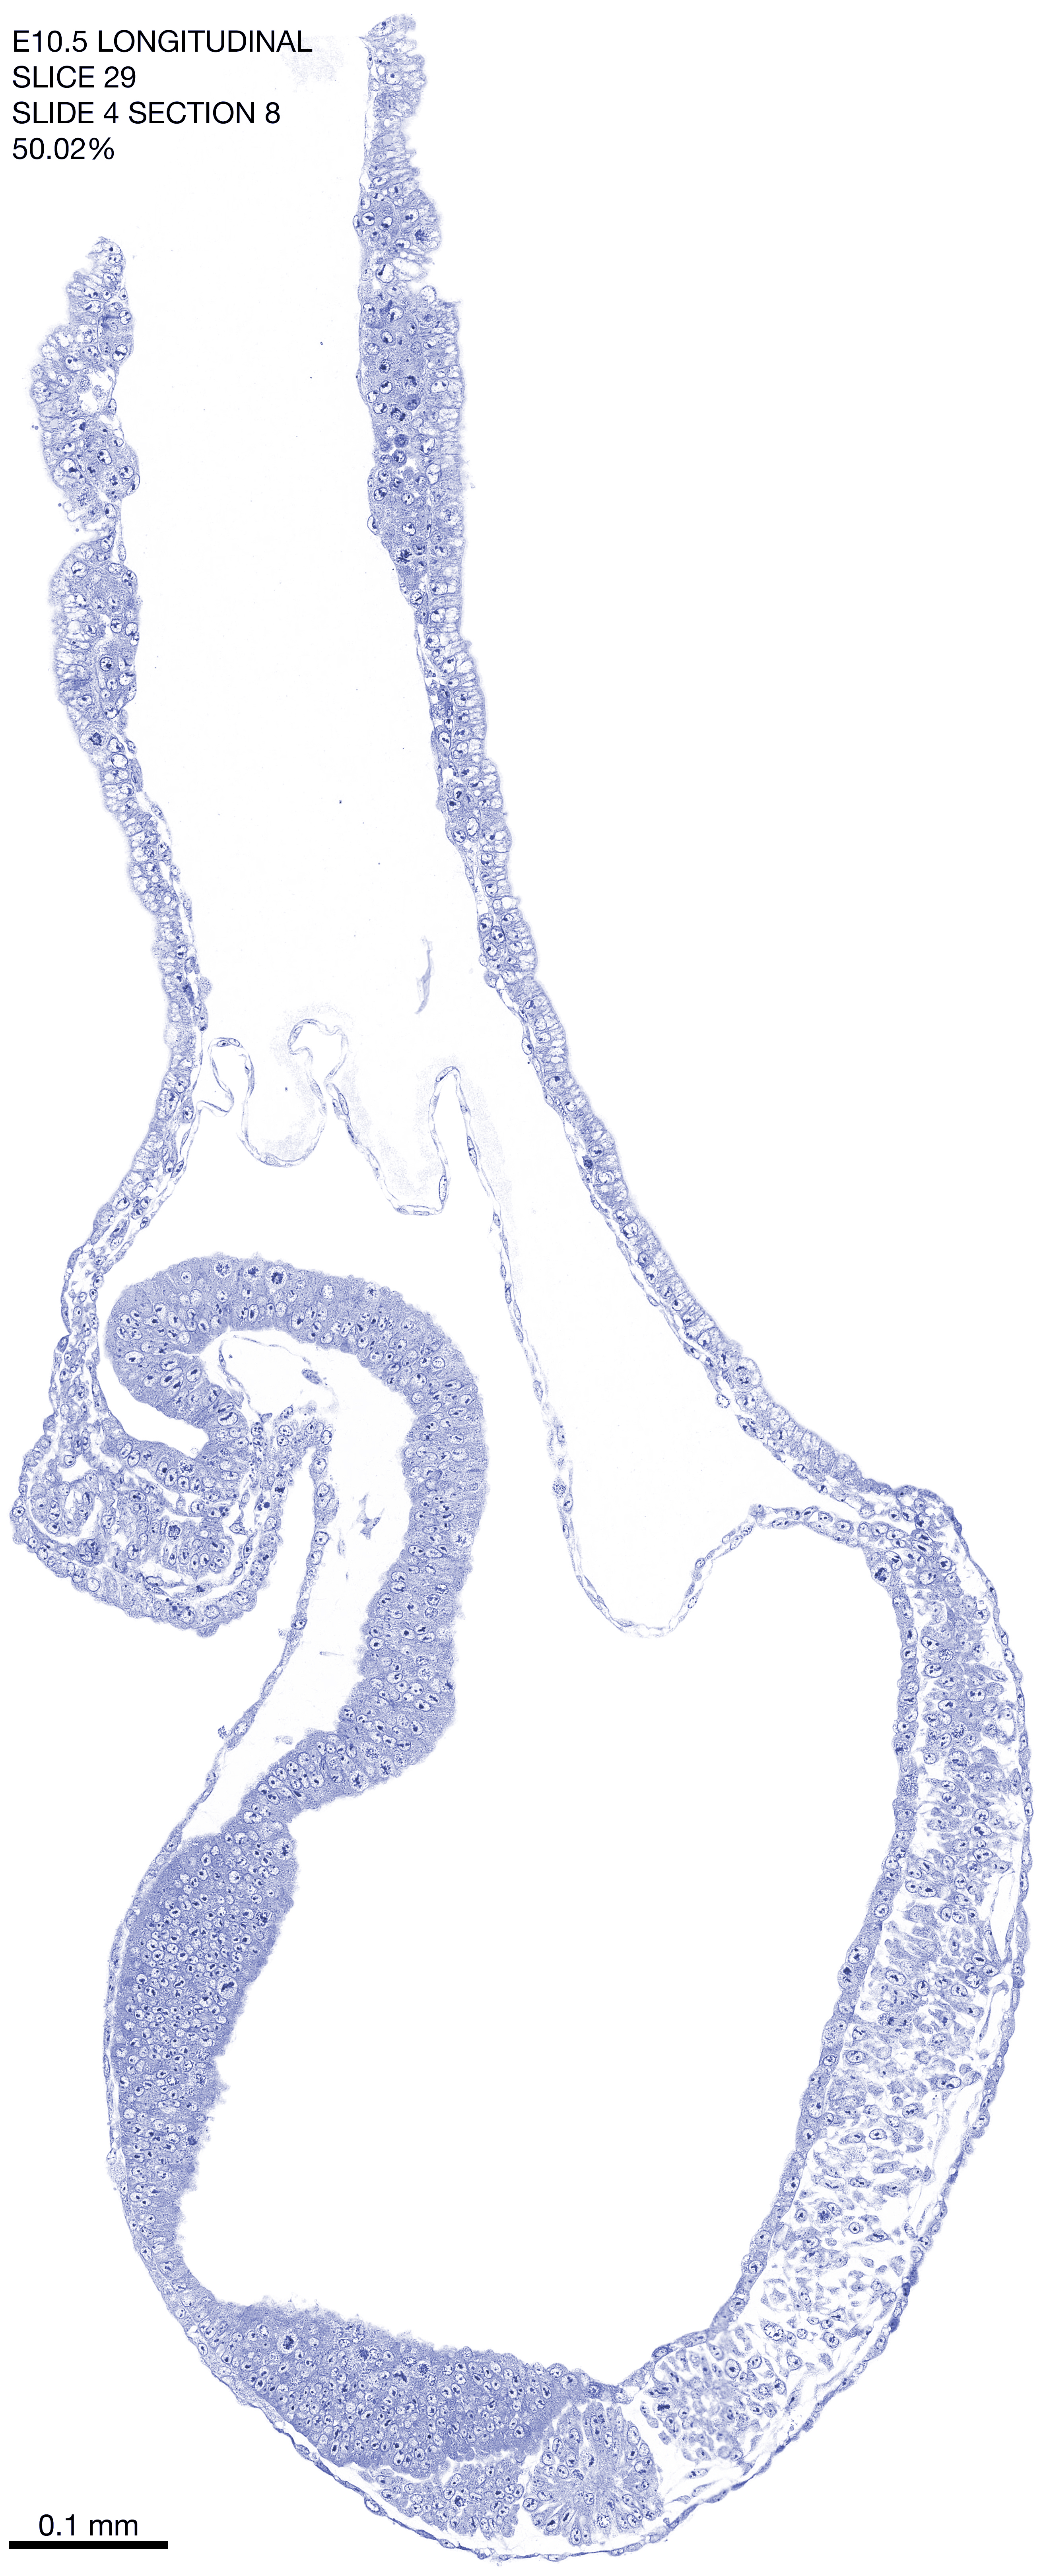

E10.5 Longitudianal Archive This page contains jpg files of ALL SLICES (each 3µm thick) that were scanned of the E10.5 longitudinally cut specimen. Download: Large | High Res Download: Large | High Res Download: Large | High Res Download: Large | High Res Download: Large | High Res Download: Large | High Res Download: Large | High Res Download: Large | High Res Download: Large | High Res Download: Large | High Res Download: Large | High Res Download: Large | High Res Download: Large | High Res Download: Large | High Res Download: Large | High Res Download: Large | High Res Download: Large | High Res Download: Large | High Res Download: Large | High Res Download: Large | High Res Download: Large | High Res Download: Large | High Res Download: Large | High Res Download: Large | High Res Download: Large | High Res Download: Large | High Res Download: Large | High Res Download: Large | High Res Download: Large | High Res Download: Large | High Res Download: Large | High Res Download: Large | High Res Download: Large | High Res Download: Large | High Res Download: Large | High Res Download: Large | High Res Download: Large | High Res Download: Large | High Res Download: Large | High Res Download: Large | High Res Download: Large | High Res Download: Large | High Res Download: Large | High Res Download: Large | High Res Download: Large | High Res Download: Large | High Res Download: Large | High Res Download: Large | High Res Download: Large | High Res Download: Large | High Res Download: Large | High Res Download: Large | High Res Download: Large | High Res Download: Large | High Res Download: Large | High Res Download: Large | High Res Download: Large | High Res Download: Large | High Res